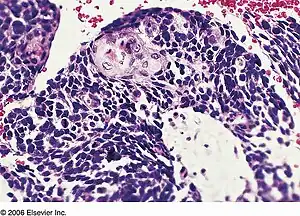

| Combined small cell lung carcinoma containing a component of squamous cell carcinoma | |

Combined small cell lung carcinoma (or c-SCLC) is a form of multiphasic lung cancer that is diagnosed by a pathologist when a malignant tumor, arising from transformed cells originating in lung tissue, contains a component of;small cell lung carcinoma (SCLC), admixed with one (or more) components of any histological variant of non-small cell lung carcinoma (NSCLC) in any relative proportion.[1][2][3]